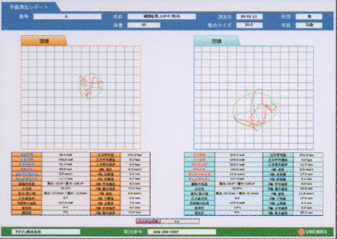

平衡機能検査

静止立位状態での重心動揺軌跡を動画で記録する事ができます。

重心動揺検査

重心の動揺奇跡を動画で経過観察や記録ができます。

動画で記録出来る事により、重心動揺計以外の用途にも使用でき、各機能訓練の現場でも経過観察に活用できます。

主な検査項目 D250 平衡機能検査

重心動揺計 250点

○外周面積・矩形面積・実行値面積

○総軌跡長・単位軌跡長・単位面積軌跡長

○動揺中心変位

○ロンベルグ率

○めまい・平衡障害や機能回復訓練の評価

データベース

データベース化されたデータを利用し比較できます。検査データは、測定日時毎に追加記録されていき、以前のデータと現在のデータを画像で比較検討できます。治療や訓練による改善状態を被験者に対して視覚的な説明が行えます。